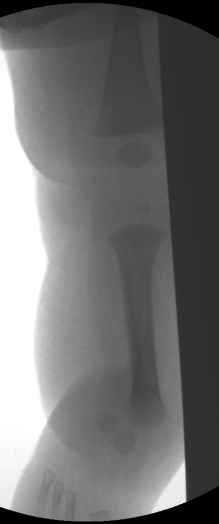

Ув.коллеги, размещаю это сообщение по просьбе друга-коллеги, в надежде услышать любые мнения и замечания по этому случаю. В приложении фото и имеющиеся снимки 3-х месячного мальчика(сейчас ему уже полгода). Родителей интересует буквально все:в какие сроки, где(и у нас в стране, и за рубежом), в какой последовательности надо решать проблему, существуют ли какие то целевые программы, где накоплен наибольший опыт лечения таких детей.. всем откликнувшимся заранее спасибо.